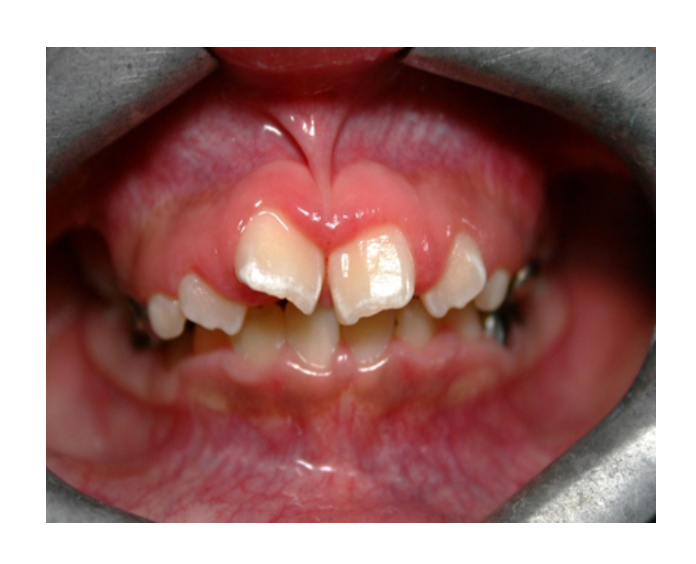

Mordida Cruzada anterior unidental